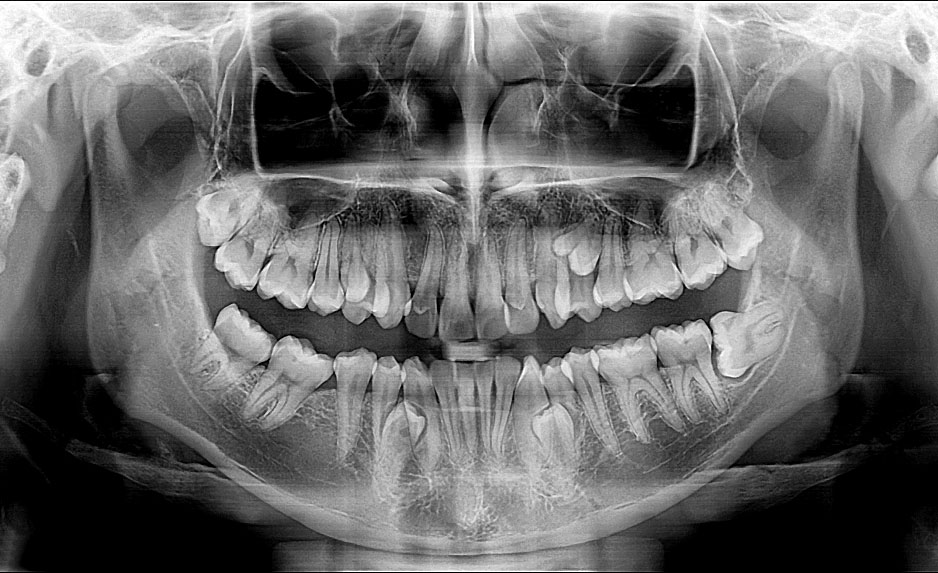

Paciente de sexo masculino de 23 años de edad, sin antecedentes médicos. En la consulta refirió, percibir una elevación en el lado izquierdo del paladar. Al examen clínico se observó aumento de volumen en la encía palatina de las premolares 24 y 25, de consistencia firme, sin alteración de color; no refirió molestia a la palpación. Al analizar la ortopantomografía se identificaron otros dientes supernumerarios (Fig. 1 - Ver en la resolución original).

Se solicitó la tomografía computarizada cone bean (CBCT) para examinar la orientación, tamaño del diente, la relación con los demás dientes y estructuras vecinas. En el examen tomográfico se identificó su ubicación intraósea en el área palatina, entre las piezas dentales 24 y 25, proyección de la corona hacia palatino y apical en vestibular, y distancia al seno maxilar (Fig. 2).

Diversas anomalías dentarias pueden presentarse como variación al número de dientes, tamaño, forma, estructura y posición. Esta variación en la fórmula dental es un hallazgo poco común en la práctica clínica; su permanencia en los maxilares podría desarrollar complicaciones como caries, maloclusiones, rotaciones dentales, problemas periodontales y quistes.(1,10) Estudios de Ramezani y otros(11) y Buchanan y otros(12) refieren que el uso del CBCT, como herramienta auxiliar para el diagnóstico más preciso para conocer la morfología y ubicación de los dientes supernumerarios; detectar cambios en la densidad del hueso y observar lesiones periapicales que no se aprecian en las radiografías convencionales.

La ortopantomografía debe ser el examen de rutina, para valorar la presencia de enfermedades en los maxilares. Si bien la presencia de dientes supernumerarios no genera sintomatología, el clínico tiene que valorar su localización y permanencia, debida a que podría causar diversas complicaciones en las estructuras adyacentes a los supernumerarios. La tomografía computarizada cone bean brinda mayor precisión para identificar las características anatómicas de los dientes supernumerarios, lo que permite planificar un adecuado tratamiento quirúrgico si el caso lo requiere.